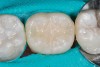

(6.) Restoration of tooth No. 19.

Figure 6

Higher viscosity bulk-fill composites can be used up to the occlusal surface, however. Two clinical cases using the bulk-fill composites Tetric EvoCeram Bulk Fill and SonicFill are presented in Figure 2 through Figure 6. Limitations when placing a high-viscosity bulk-fill composite include difficulty of condensing and esthetic restraints. Condensing a high-viscosity resin composite ensures adequate adaptation to the tooth preparation and sufficient interproximal contacts. Condensing 4 mm of composite is more difficult than condensing 2 mm. To ensure adequate interproximal contacts, a sectional or circumferential matrix with an inciso-gingival curvature can be used to obtain a tight area of contact gingival to the marginal ridge. A ring should be used to help separate the teeth and improve the tightness of the contact area.

An esthetic limitation of bulk-fill composites is that most materials are available in a small selection of shades. In addition, some of these materials have slightly higher translucency than conventional posterior composites. The esthetics achieved by these composites should be sufficient for posterior restorations for most patients.